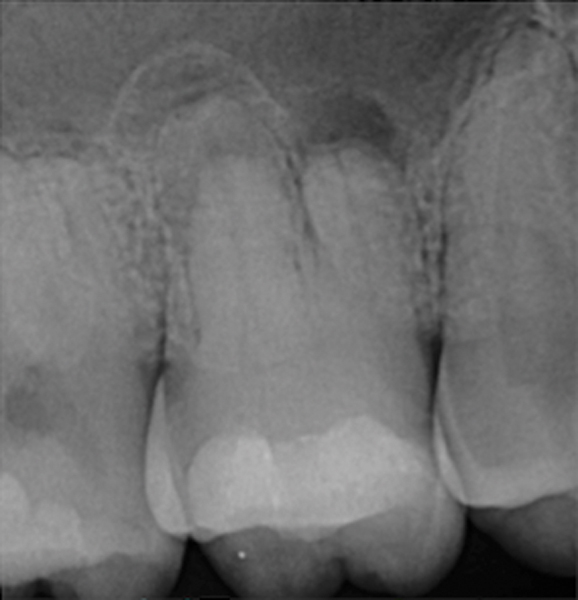

Figure 4. AND Figure 5. Before and after radiographs of bioceramic sealer hydraulically moved with the gutta-percha point. Note that the cold hydraulic technique results in lateral canal “puffs” similar to the warm vertical technique. Courtesy of Dr. Mohammed A. Alharbi.

Figure 4

Figure 5

Pre-mixed BC Sealer is the only pure medical-grade bioceramic product available as a sealer for endodontic obturation. It has the same basic chemical composition as the other pre-mixed bioceramic products, but it is less viscous, which makes its consistency ideal for sealing root canals. It is used with a gutta-percha point, which is impregnated on the surface with a nano particle layer of bioceramic. The gutta-percha is used primarily as the delivery device (plugger) (Figure 1 through Figure 3) to allow hydraulic movement of the sealer into the irregularities of the root canal and accessory canals (Figure 4 and Figure 5).